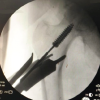

Both patients described how they reluctantly went down the waterslide with their fathers behind them at the back. Both girls apparently were trying to slow themselves down with their legs upfront. The two girls were unable to bear weight after sliding. On physical evaluation, both refused to bear weight on their left legs, and leg rolling tests was positive. Both had no other complaints. After physical clearance, the girls were X-rayed and diagnosed with hip fractures. The 10-year-old suffered a Delbet Type II fracture (Fig. 1a, b) while the 12-year-old had a Delbet Type III fracture (Fig. 2a, b). Both were admitted to the Pediatric Orthopedic Unit in our institution and were surgically treated, approximately 4 days after their initial injury, with closed reduction and internal fixation. The 10-year-old patient with the Delbet Type II fracture was fixated using NAa LCP Pediatric Hip Plate 5.0 (DePuy Synthes, Raynham, MA, USA) (Fig. 1c, d), as recommended by Beaty et al. [1]. The 12 years old patient, who suffered from the Delbet Type III fracture, was overweight for her age at roughly 65 kg. The surgeon’s intra-operative decision was to fixate her with more robust hardware, using an adult Compression Hip Screw (Smith and Nephew Richards, Memphis, TN, USA) augmented with a 7.5 mm cannulated screw to prevent rotation (Fig. 2c , d).